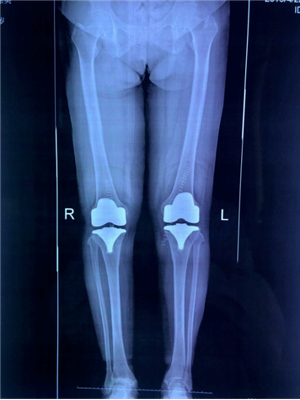

據(jù)了解,Vanguard CR E1假體為后交叉保留型假體,患者術后本體感覺良好,無需做髁間截骨并保留了骨量,手術有標準、Liped、AS 共3種墊片可供選擇,E1墊片更耐磨(E1墊片在原有材料基礎上將維他命E滲入高交聯(lián)聚乙烯,中和去除自由基,實現(xiàn)超低磨損,保持機械強度,提供優(yōu)異的抗氧化穩(wěn)定性)。

?。ㄊ中g前、手術后對比)

5月29日,徐阿姨如期進行了雙側(cè)全膝關節(jié)同期置換術。術中發(fā)現(xiàn)徐阿姨膝關節(jié)退變嚴重,有大量的滑膜軟骨瘤,清除病變后又發(fā)現(xiàn)她前交叉韌帶缺失后交叉韌帶纖細,即決定采用限制性較高的E1 AS墊片,該假體極大的提高了手術安全性,降低了手術風險和創(chuàng)傷,手術歷時2小時,患者術后恢復良好。手術后第二天,徐阿姨就可以扶著助步器下地活動,目前已可以徒步行走、上下樓梯。